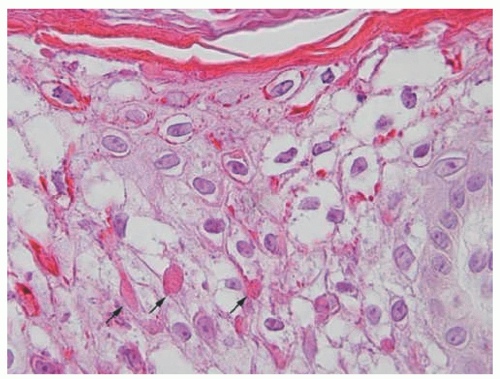

acanthosis. Focal parakeratosis, hypogranulosis, and exocytosis of neutrophils are variably present (Figure 7-14).47,48,49 In erythrodermic cases, parakeratosis can be confluent. A perivascular lymphohistiocytic infiltrate may be present in the superficial dermis.50 Periodic acid-Schiff staining demonstrates densely staining granules in upper epidermal layers.8 A microscopic evaluation of affected hair shafts reveals trichorrhexis invaginata, with a telescoping of the distal hair shaft into the proximal shaft.43 Other hair shaft findings, such as trichorrhexis nodosa, pili torti, and “matchstick” abnormality, can also be seen.